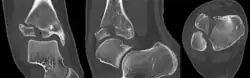

A Tillaux fracture is a Salter–Harris type III fracture through the anterolateral aspect of the distal tibial epiphysis.[1] It occurs in older adolescents between the ages of 12 and 15 when the medial epiphysis had closed but before the lateral side has done so,[2] due to an avulsion of the anterior inferior tibiofibular ligament, at the opposite end to a Wagstaffe-Le Fort avulsion fracture

The fracture commonly results from an abduction-external rotation force, causing the anterior tibiofibular ligament to avulse the anterolateral corner of the distal tibial epiphysis resulting in a Salter Harris Type III fracture.

It occurs in older children at the end of growth. Variability in fracture pattern is due to progression of physeal closure as anterolateral part of distal tibial physis is the last to close. When the lateral physis is the only portion not fused, external rotation may lead to Tillaux or Triplane fractures.[3]